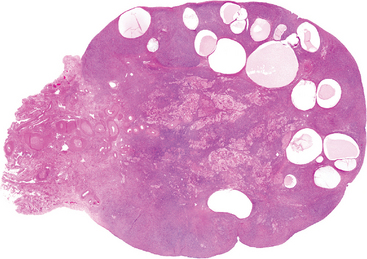

Morphology. The characteristic serous tumor may present on gross examination as either a cystic lesion in which the papillary epithelium is contained within a few fibrous walled cysts (intracystic) (Fig. 22-37A), or projecting from the ovarian surface. Benign tumors typically present with a smooth glistening cyst wall with no epithelial thickening or with small papillary projections. Borderline tumors contain an increased number of papillary projections (Fig. 22-37A and C). Bilaterality is common, occurring in 20% of benign serous cystadenomas, 30% of serous borderline tumors, and approximately 66% of serous carcinomas. A significant proportion of both serous borderline tumors and malignant serous tumors involve (or originate from) the surface of the ovary (Fig. 22-37C). On histologic examination, the cysts are lined by columnar epithelium, which has abundant cilia in benign tumors (Fig. 22-38A). Microscopic papillae may be found. Serous borderline tumors exhibit increased complexity of the stromal papillae, stratification of the epithelium and mild nuclear atypia, but destructive infiltrative growth into the stroma is not seen (Fig. 22-38B).75 This epithelial proliferation often grows in a delicate, papillary pattern referred to as “micropapillary carcinoma” and is thought to be the precursor to low-grade serous carcinoma (Fig. 22-38C). Larger amounts of solid or papillary tumor mass, irregularity in the tumor mass, and fixation or nodularity of the capsule are important indicators of probable malignancy (see Fig. 22-37B). These features are characteristic of high-grade serous carcinoma, which microscopically exhibits even more complex growth patterns and infiltration or frank effacement of the underlying stroma (Fig. 22-38D). The individual tumor cells in the high-grade carcinomas display marked nuclear atypia, including pleomorphism, atypical mitotic figures, and multinucleation. The cells may even become so undifferentiated that serous features are no longer recognizable. Concentric calcifications (psammoma bodies) characterize serous tumors, but are not specific for neoplasia. Ovarian serous tumors, both low- and high-grade, have a propensity to spread to the peritoneal surfaces and omentum and are commonly associated with the presence of ascites. As with other tumors, the extent of the spread outside the ovary determines the stage of the disease.

image

FIGURE 22-37 A, Serous borderline tumor opened to display a cyst cavity lined by delicate papillary tumor growths. B, Cystadenocarcinoma. The cyst is opened to reveal a large, bulky tumor mass. C, Another borderline tumor growing on the ovarian surface (lower).